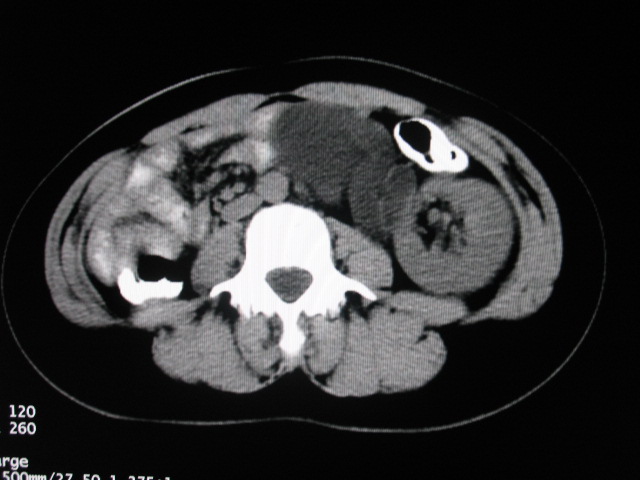

女,28岁,自觉腹部包块一年余

支持;左侧双肾盂双输尿管畸形,其中一输尿管末端梗阻并输尿管肠管样扩张迂曲、肾盂囊状扩张积水。

左双肾盂输尿管畸形.其一输尿管远端输尿管囊肿引起一肾盂输尿管积水.

考虑左侧双肾盂双输尿管畸形,其中一输尿管末端梗阻并输尿管肠管样扩张盂曲、肾盂囊状扩张积水。

术后证实是左侧双肾盂双输尿管畸形,巨输尿管巨肾盂症